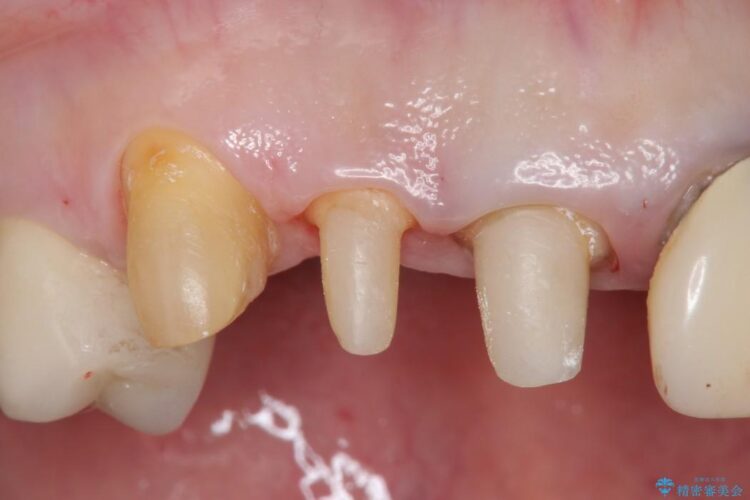

上顎右側の前歯2本のかぶせ物部分の再治療と犬歯に発生していた虫歯治療を主訴に来院されました。

前歯のかぶせ物に関しましては、内面が金属で覆われているため歯茎にその色が透けて見えるという審美的な問題と、かぶせ物と歯の境界が不適合であるという問題がありました。

犬歯の虫歯につきましては、何度も詰め物治療が繰り返されている痕跡があり今回虫歯を取りきるにあたり歯の強度に不安が残るため前歯と同時にかぶせ物の治療をしていくことを計画しました。